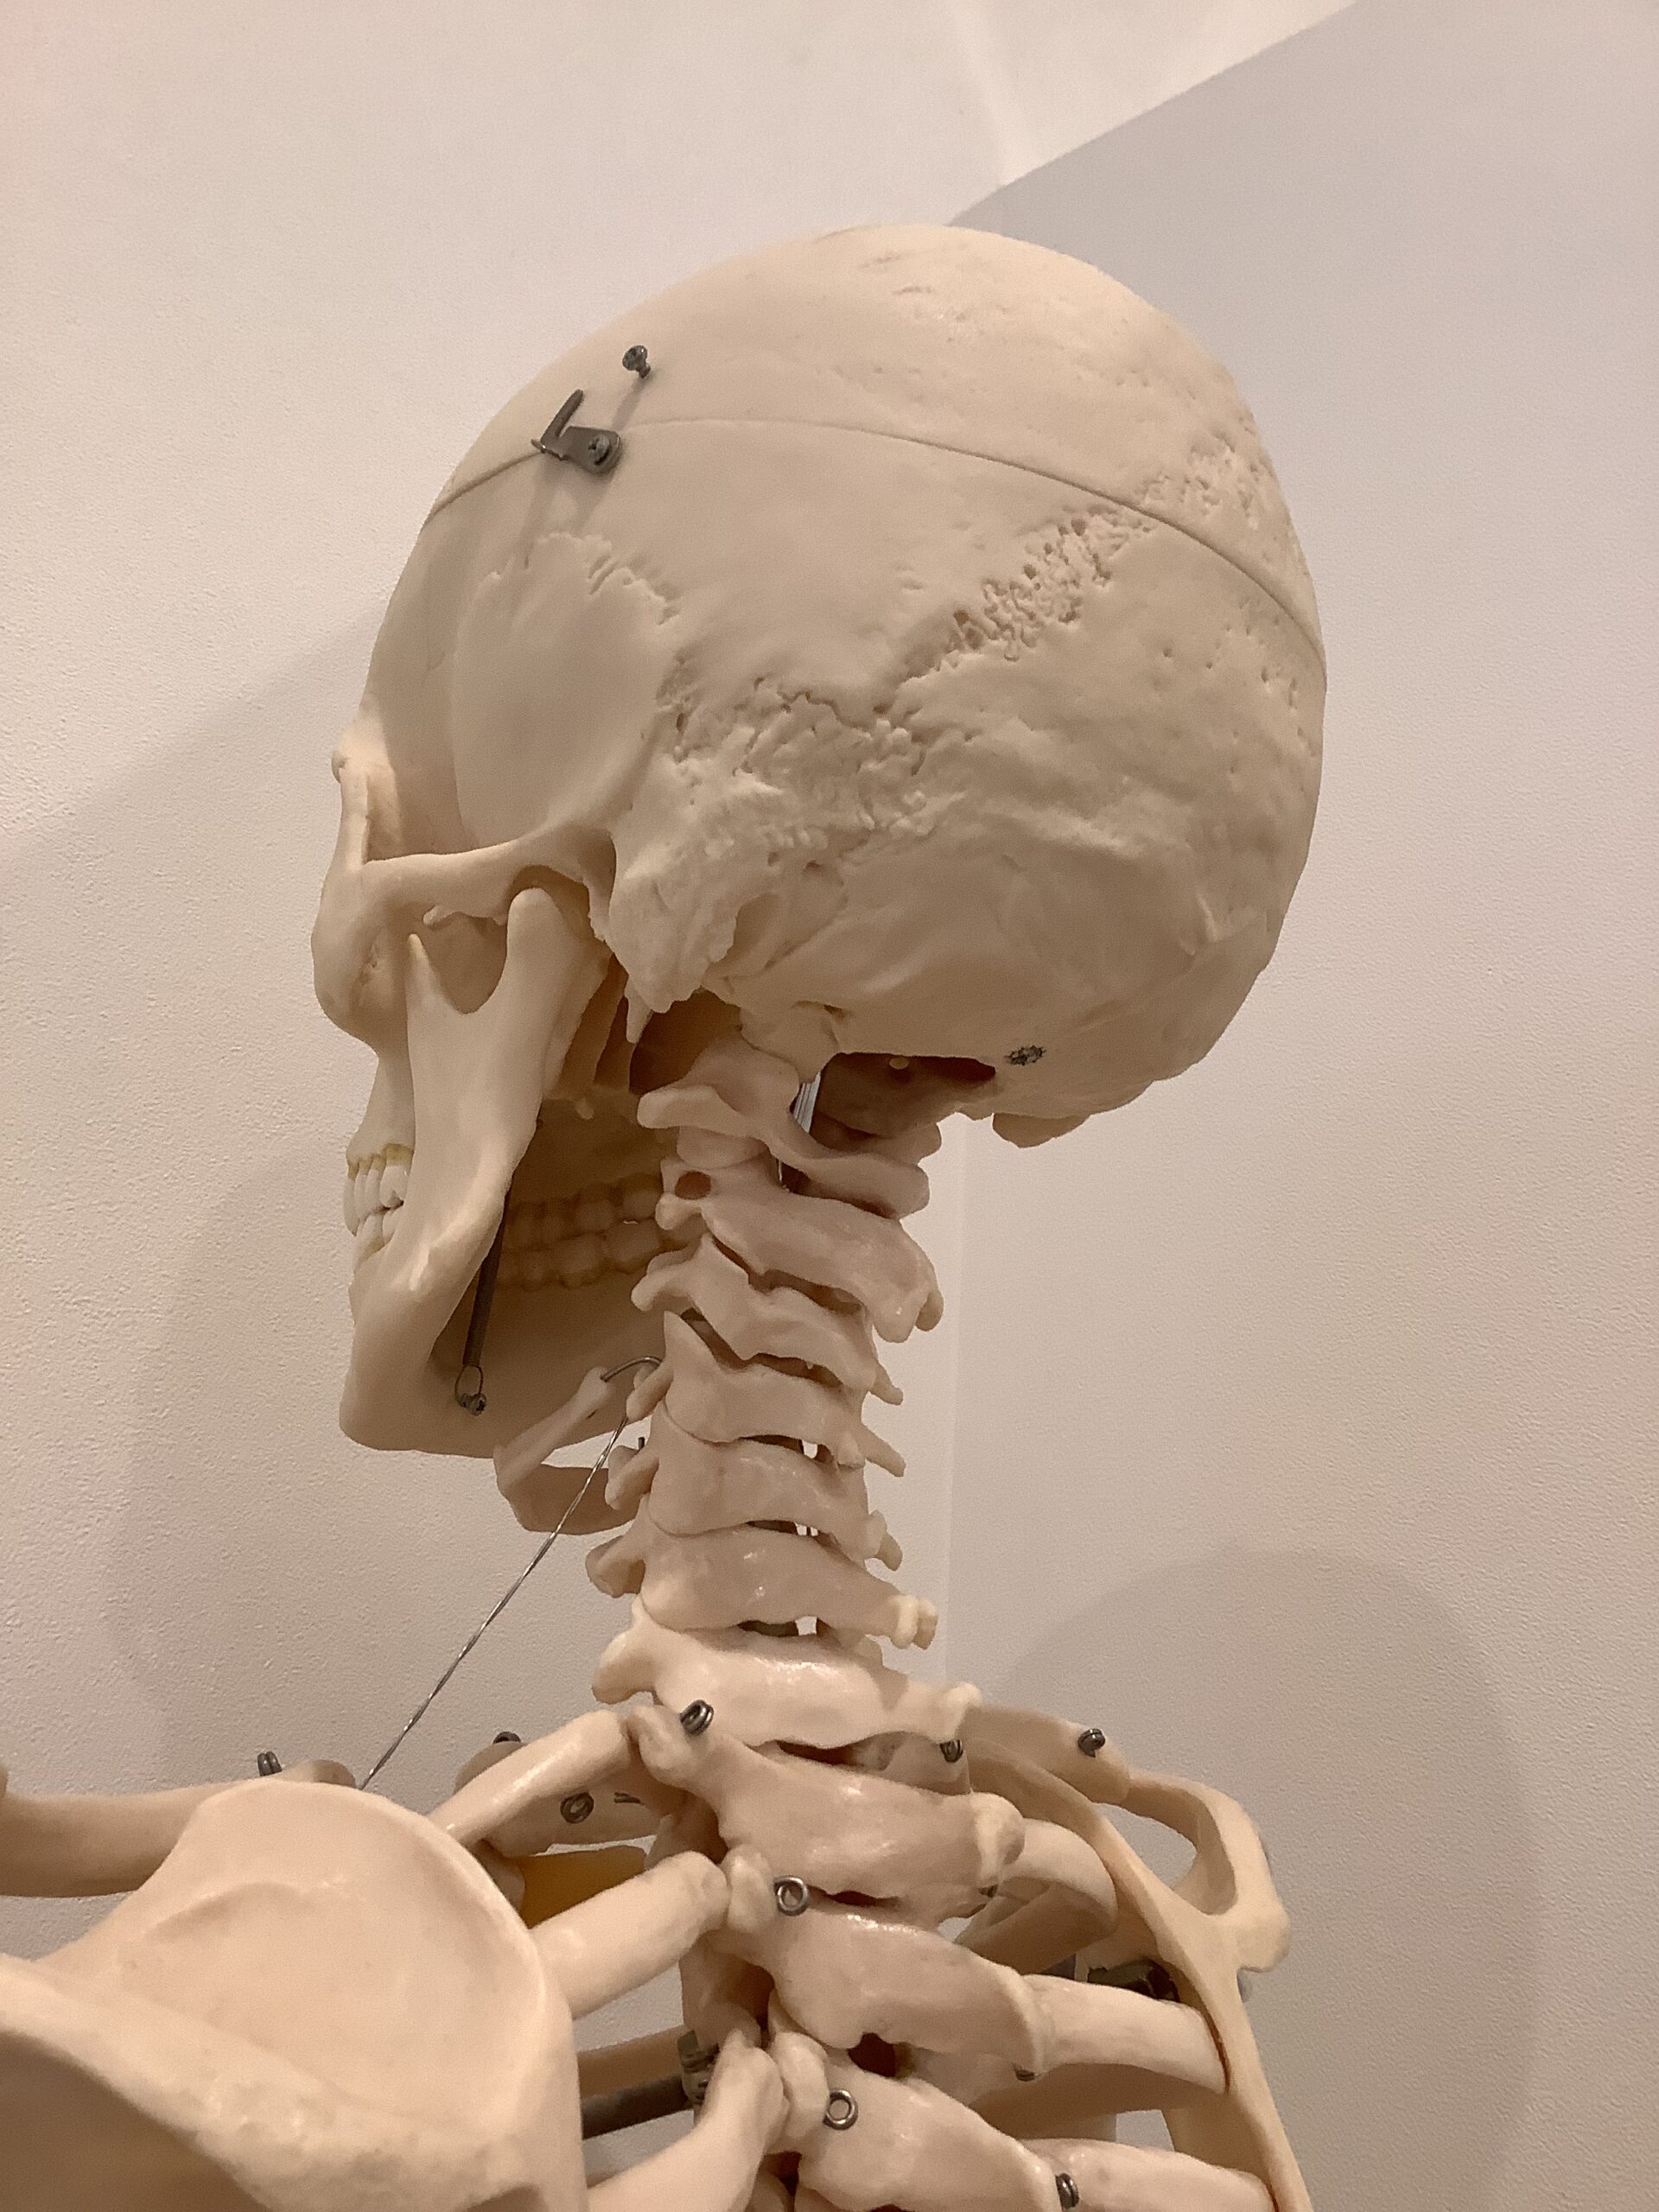

首に強い張りやコリを感じている方に共通する歪みは、首にある頚椎、背骨の胸椎が後弯いわゆる猫背となり、顔だけが前に出ている状態です。また、頭の頭蓋骨のうちの後頭骨が下方へ下がり、頭の後ろにある大後頭直筋などの筋肉がガチガチに硬い状態になっている方が多いです。首の不調をそのまま放っておくと、硬くなった筋肉がより首の骨格を歪ませるため、痛みや首の可動域等の不調も引き起こします。さらには、首とつながっている背中や肩の不調にもつながるケースは多くあります。

マッサージで改善されない首の不調は根本の骨格の調整から。頚椎や胸椎を整え筋肉を緩めやすくする土台を作りましょう。骨格の歪みを検査する骨格ドックと骨格の調整がセットになったメニューは、こちらからご覧ください。